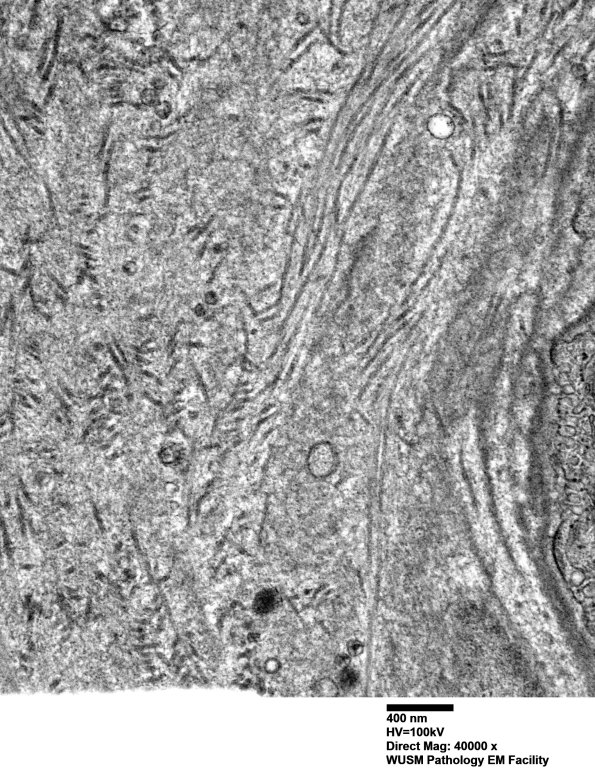

The endoneurial vessel shown here is expanded by collagen deposition with a small contribution by fragments of basal lamina. (electron micrographs)